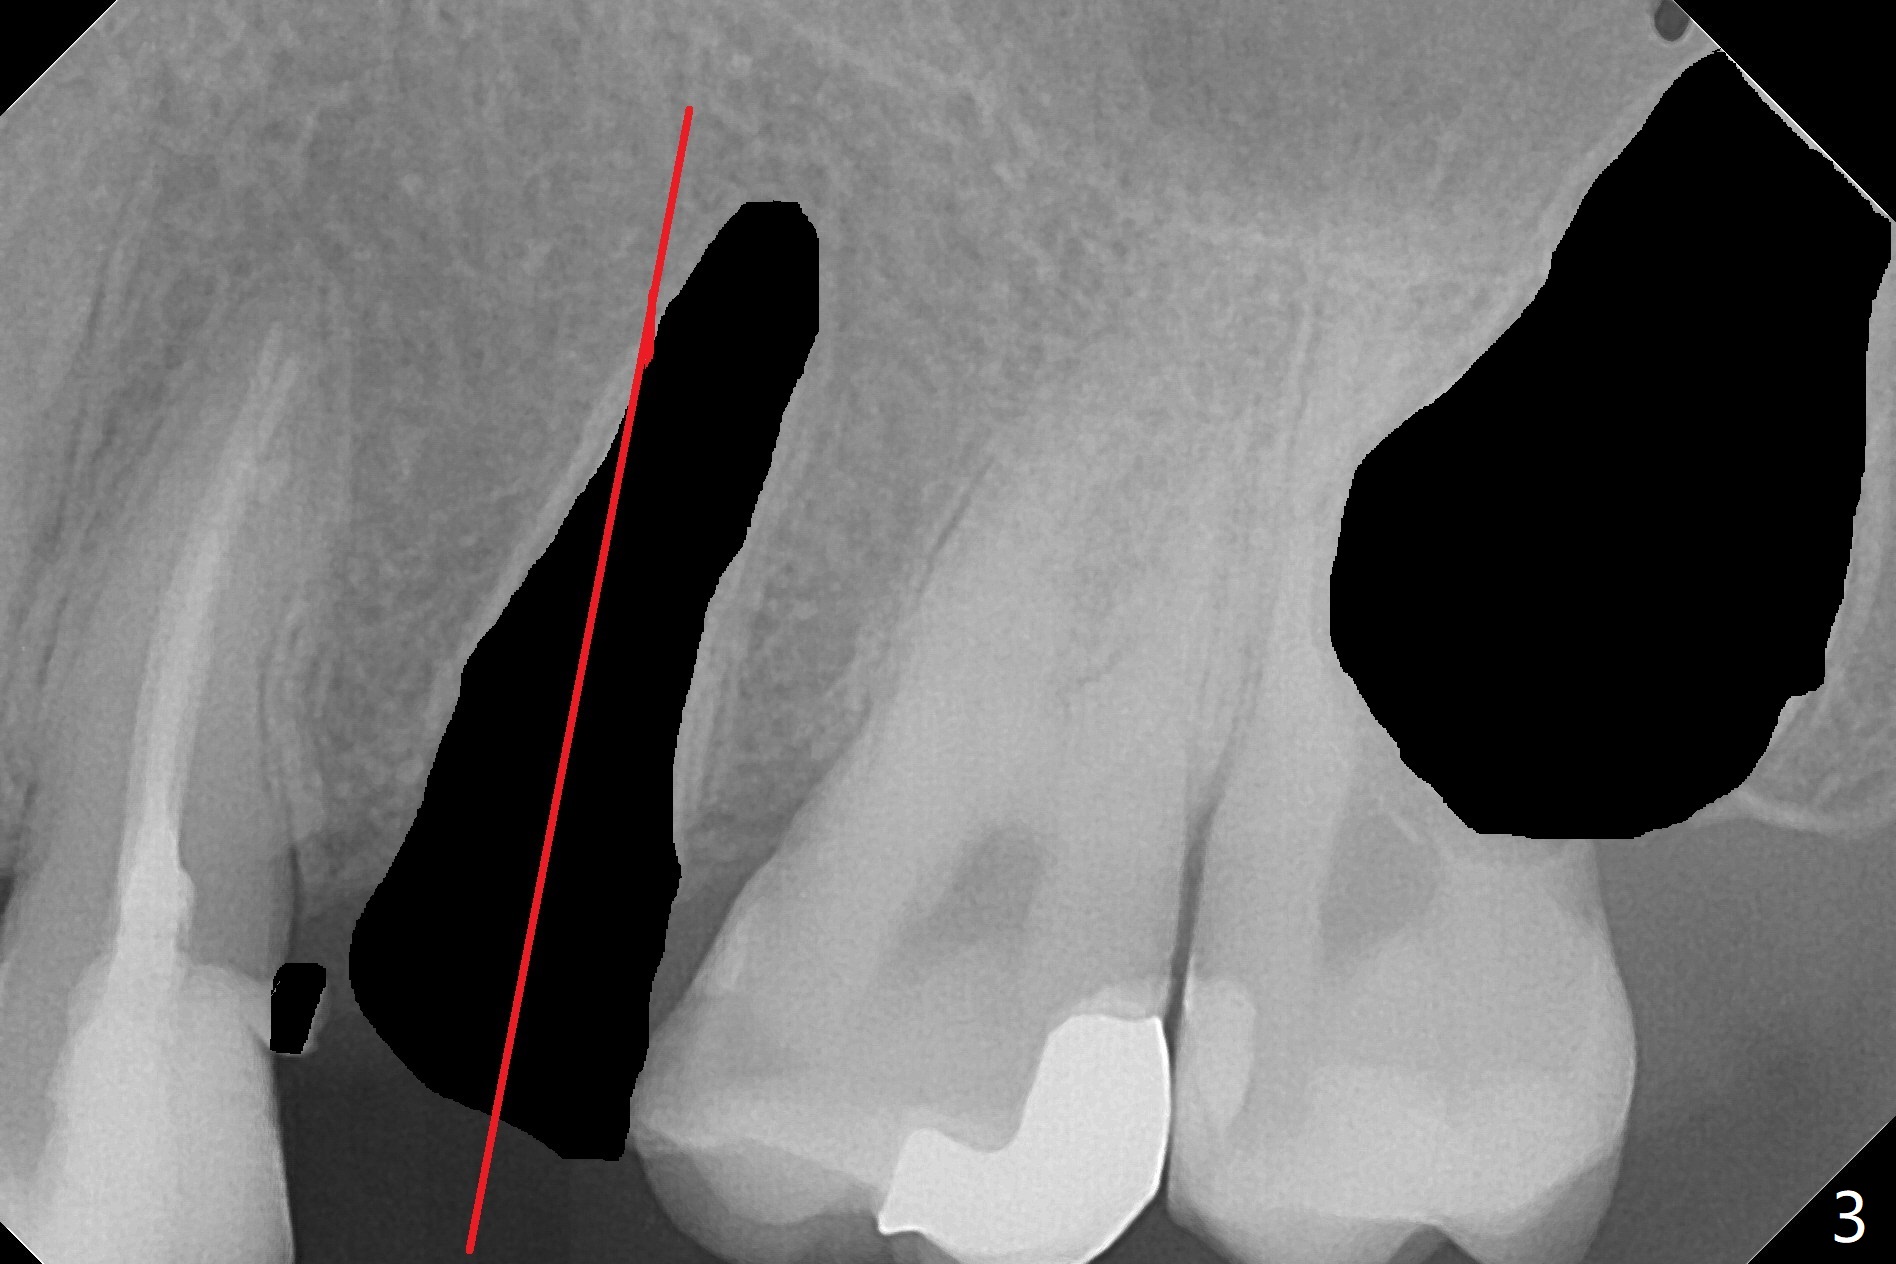

A 27-year-old man returns to clinic with #13 subgingival fracture, which is associated with Class III malocclusion and anterior open bite (Fig.1). Both #1 and 16 seem to be buccal to the 2nd molars, causing root resorption (Fig.1 *). Since the root of the 2nd premolar tilts distal, osteotomy for an implant will be in the mesiopalatal aspect of the extraction socket (Fig.2,3 red). Following implant placement, #16 will be extracted (Fig.3 black), laying foundation to distalize and intrude #14 and 15 to make space for #13 implant crown and reduce anterior open bite and posterior tooth overloading (Fig.4 arrow). No Deviation Clindamycin Xin Wei, DDS, PhD, MS 1st edition 08/25/2020, last revision 09/08/2020